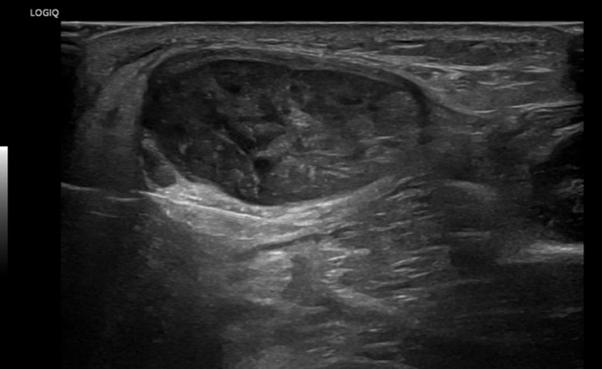

Ultraljud är ett speciellt radiologiskt område i snabb utveckling, som har fantastiska möjligheter. Enkelt, billigt, snabbt, patientnära. Jag kvalar väl in som ”ultraljudsnörd” då jag tillbringar större delen av min vardag med en transducer i handen. (Dessutom är jag ordförande också i svenska ultraljudsföreningen, SFMU.) Men jag har verkligen inte något emot att ni kliniska kollegor tar upp proben, dock under-

skattar ni ofta hur mycket träning som krävs för att bli bra. Första rådet – bestäm er om ni gör diagnostiskt eller kliniskt ultraljud! Diagnosgrundande ultraljud är det vi gör på röntgen. Då ställs högre krav på kompetens, evidens, maskiner och undersökningsteknik och inte minst så måste undersökningen journalföras, dvs bilderna ska lagras korrekt (PACS). Kliniskt ultraljud är ett komplement till status, typ anatomisk kartläggning inför en operation eller enkla frågor som finns ledutgjutning: ja/nej. Då kan ni journalföra i text som del av status. Diagnostiskt ultraljud ska utföras på standardiserat sätt och här finns tydliga direktiv om hur samt vilken träning och kompetens som krävs (se hemsidor till europeiska ultraljudsföreningen samt föreningen för muskuloskelettalradiologi: www.efsumb.org samt www.essr.org/ subcommittees/ultrasound/). Dessutom behövs teknisk support till både upphandling och maskinservice – för precis som för bilar krävs årlig service och kontrollbesiktning. Man har skyldigheter oavsett om man äger en bil eller en ultraljudsapparat. Det är heller inte läkarjobb att knappa personnummer eller tvätta prober, utan se till att ha undersköterskor som assisterar. Som ultraljudsentusiast går det inte att vara protektionistisk – teknikutvecklingen har exploderat och de enklaste maskinerna blir allt billigare. Både sjukgymnaster och naprapater har redan hoppat på tåget och snart har väl alla pensionärsföreningar och sportbu-

ULTRALJUDSLEDDA BIOPSIER OCH INJEKTIONER

Ultraljudsanvändningen har expanderat exponentiellt i den muskuloskeletala arenan på senare år av flera skäl, bland andra förbättrad säkerhet, enkelhet och minskade kostnader. Dessutom använder man inte joniserande strålning.19 Utöver att ultraljudsundersökning är användbar för diagnostik av en stor grupp muskuloskeletala åkommor kan tekniken även används som ett mycket effektivt verktyg för att vägleda administrering av läkemedel, vid punktion och biopsi samt för ablation

av muskuloskeletala tumörer genom att följa placeringen av nålen i realtid.20 Bättre noggrannhet och effektivitet har rapporterats för många ultraljudsvägledda åtgärder jämfört med åtgärder utförda enbart med hjälp av palpation. Utvecklingen av ultraljudsteknik och träning i ultraljudshantering gör att den kommer att fortsätta att ha en viktig roll inom muskuloskeletal sjukdomshantering.21